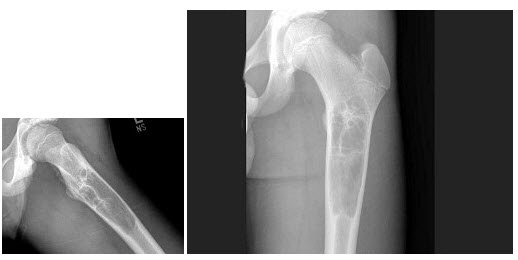

33、单项选择题

女,14岁,右大腿上部轻度疼痛1周,结合图像,最可能的诊断是()

A.骨囊肿

B.骨巨细胞瘤

C.嗜酸性肉芽肿

D.动脉瘤样骨囊肿

E.以上都不是

D.红外线